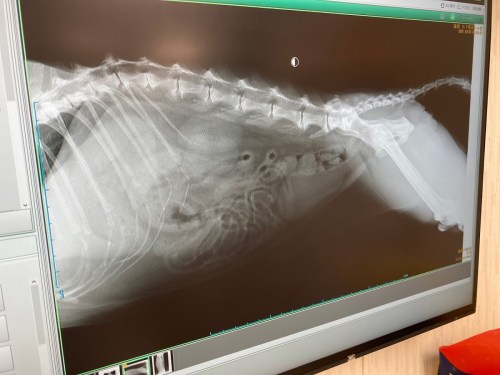

ちなみにこれは私の中身を伴った大きなお腹のビックレントゲン写真です